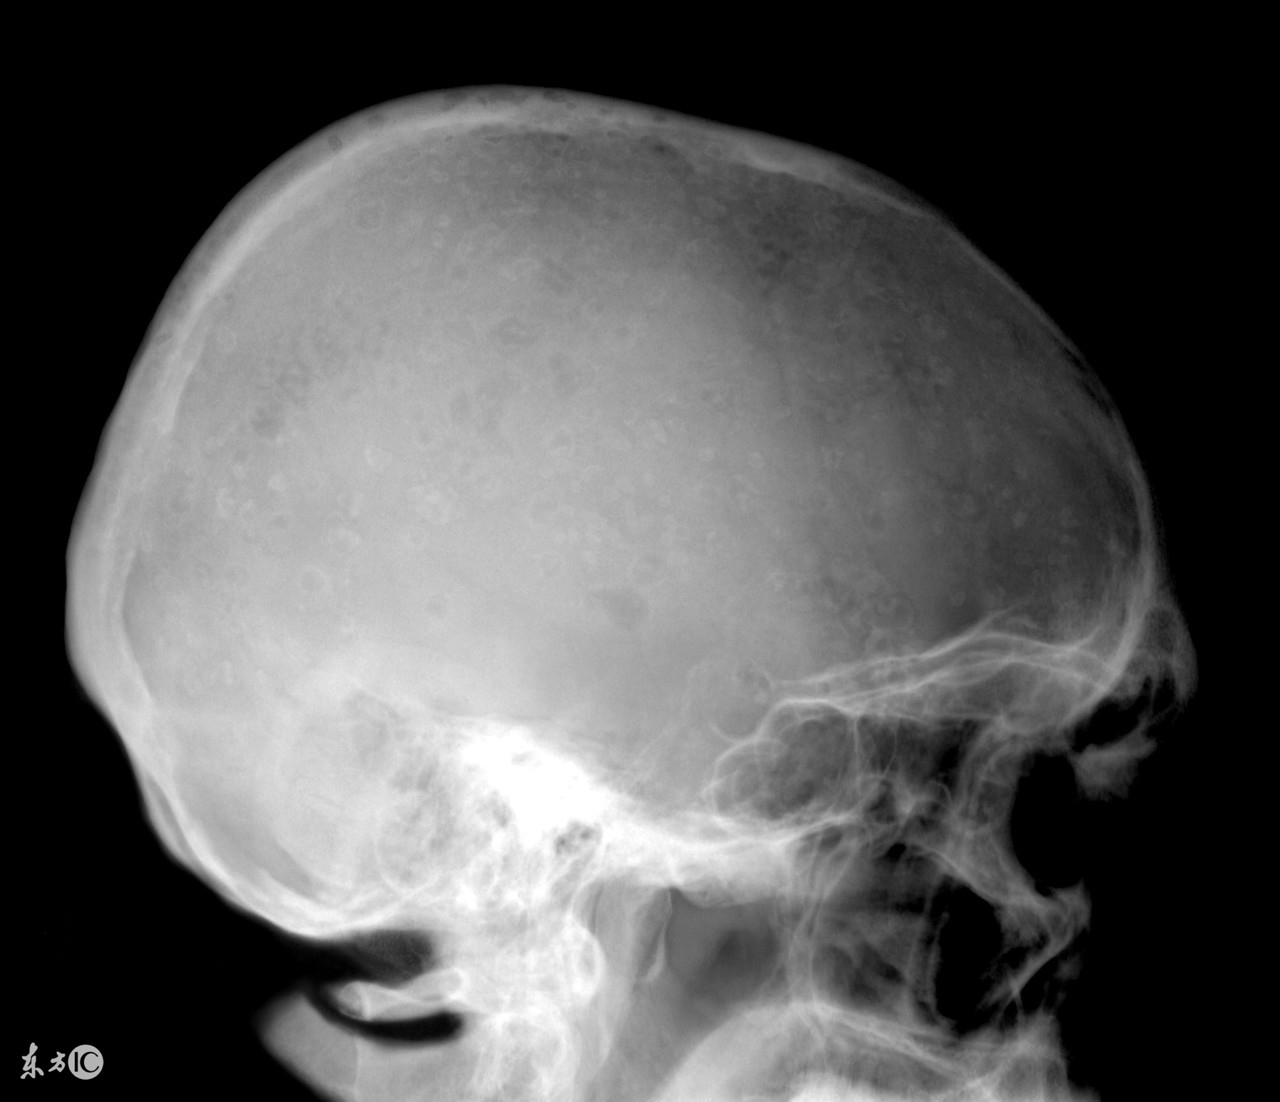

越来越多的人受到了多发性骨髓瘤的困扰,我们大家都知道,患了多发性骨髓瘤会对我们的身体和心理健康造成很大的危害,因此发现患病之后一定要积极的进行治疗,而且多发性骨髓瘤的治疗也是有一定难度的,那么,多发性骨髓瘤大概需要花费多少钱?

治疗多发性骨髓瘤费用其实和患者的病情严重程度有着密切的关联,而且较为严重的时候还会引起消化系统、血汗管系统、运动系统等多器官病变,严重可导致死亡。所以想要了解治疗多发性骨髓瘤疾病究竟需要多少钱是需要根据患者病情的严重程度才能确定,因为对于不同程度的治疗多发性骨髓瘤的方法不同,相对应的费用也是不一样的,所以当患上这种疾病之后,一定要第一时间到医院接受治疗,避免病情恶化而导致治疗难度增大,费用增多。